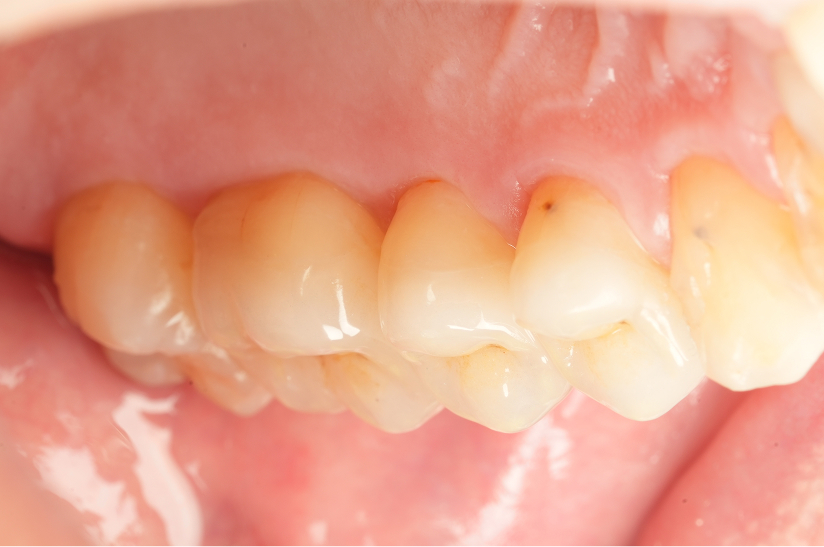

虫歯治療の症例紹介

最小限の切削量で

虫歯治療を完了させた症例

Before

After

主訴

ものが詰まって、染みるようになった。

治療内容

ダイレクトレストレーション2本

治療期間

通院回数1回

治療費用

110,000

治療の

リスク

術後に一時的な知覚過敏症状が出る可能性があります。